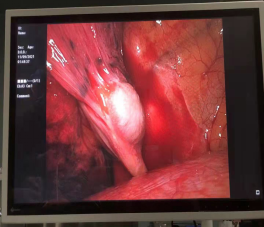

住院后,完善各项常规术前检查,积极做好手术准备,同时做好肺癌根治术准备。入院第3天,由副主任医师任军、主治医师杨金国为患者行胸腔镜单操作孔肿物切除术,胸部切口长约3厘米,术中发现肿物位于左肺下叶基底段靠近膈肌,完整将肿物切除,送快速病理检查,结果为良性病变,及时告知家属,常规病理结果为支气管源性囊肿,家属悬着的心终于放下了。

治疗方法以手术为主,预后多数良好。我院近2年接诊3例,前2例为纵隔型,该患者为肺内型,均行腔镜手术切除。